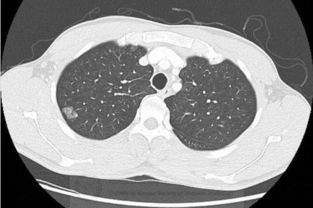

肺结节是指直径小于3cm的肺部阴影,其中直径小于1cm的称为肺小结节,直径小于0.5cm叫做微小结节。

肺结节的发生率其实较高,随着年龄的增长,发病率也有所提高。

在55-64岁人群中检查率接近2%。

肺结节的发生与抽烟、空气污染。